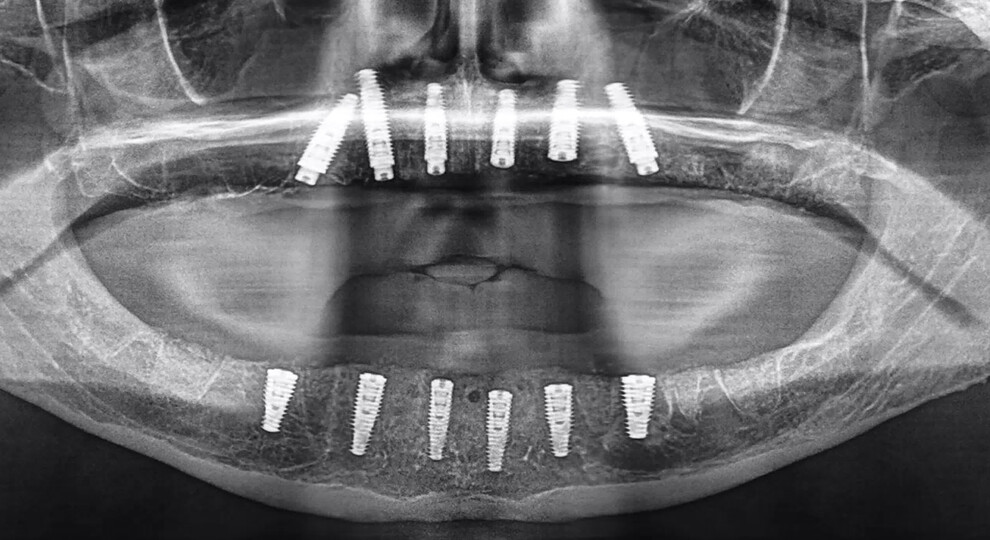

The mandibular bone reduction was completed using piezoelectric surgery (PIEZOSURGERY, mectron) and rotary instruments (Alveoplasty Surgical Kit, Meisinger) to provide adequate width and restorative space for the implant-supported restoration. Once the bone reduction had been completed, the bone-borne osteotomy guide was placed on to the mandibular ridge. The advanced AI-generated segmentation provided for an intimate fit of the guide, which was then secured with three horizontal anchor pins and guide stabilisers to immobilise the guide during the drilling process (Fig. 16a). Once the six implants had been successfully placed, the guide was removed, revealing the reduced bone and residual extraction sockets (Fig. 16b). Approximately 1 cm3 of mineralised cortical and cancellous bone was placed in the extraction sockets and remaining fenestrations. The implant stability quotient values were not adequate for immediate loading, and therefore, a two-stage protocol was chosen for the mandibular arch implants. The postoperative panoramic image revealed the successful placement of a total of 12 implants in both the mandibular and maxillary arches (Fig. 17).

Fig. 17: Post-op panoramic radiograph revealing the successful placement of 12 implants in a two-stage protocol, requiring a healing period of three to four months before uncovering.